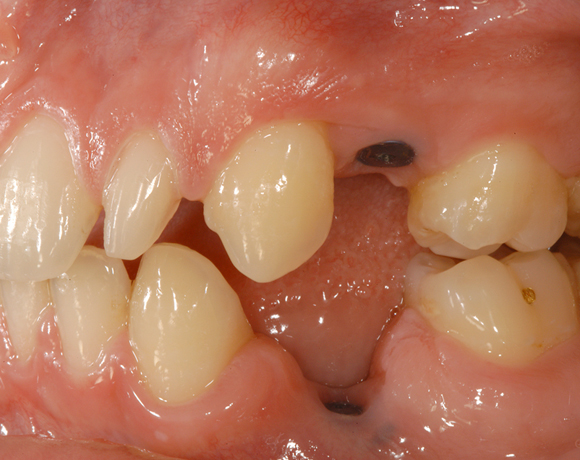

Bei diesem Patienten wurden die Nachbarzähne und das Implantat vollkeramisch versorgt.